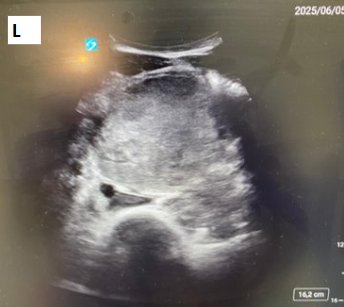

Historia clínica: Antecedentes personales: no enfermedades previas de interés, no antecedentes quirúrgicos, no alergias conocidas. Hábitos tóxicos: tabaco 1 paquete/día; cocaína, cannabis y TUSI, uso recreativo; alcohol, ocasional. Anamnesis: Paciente masculino de 28 años de aspecto atlético, que consulta por dolor abdominal de inicio súbito en epigastrio y mesogastrio, EVA 8/10, de 4-5 horas de evolución, sin otros síntomas asociados. Refiere consumo de anabolizantes (anabolizantes del GYM: boldenona, testosterona), además de proteína y creatina. Exploración: TA: 155/100 Abdomen: RHA presentes y conservados, abdomen blando, depresible, doloroso a la palpación superficial ni profunda en mesogastrio e hipogastrio. Sin signos de irritación peritoneal. Pruebas complementarias: Ecografía A pie de cama Se realiza barrido con sonda convexa; se observan dos masas lobuladas en la región del mesogastrio, heterogéneas e hiperecogénicas, derecha con área anecoica, diámetro aproximado de 16 cm, con paredes bien definidas, que no capta con Doppler. Tras control del dolor, se decide remisión al hospital de referencia, donde se completa estudio con analíticas, TAC y BAG de las lesiones: Analíticas: LDH 1,361 U/L (<300), PROTEÍNA C REACTIVA 17,19 mg/dL (<0,5), BETA-2 MICROGLOBULINA 2.903 µg/L (<2,5). BETA HCGMT 5,43 mU/mL (<5). TAC: CONCLUSIÓN: Las lesiones descritas presentan aspecto inespecífico, debiendo plantear dentro de diferentes posibilidades diagnósticas que correspondan a extensos conglomerados ganglionares o lesiones infiltrativas primarias/secundarias, incluso debiendo plantear como posibilidad tumores germinales. BAG de las lesiones eco guiada: Anatomía patológica SEMINOMA